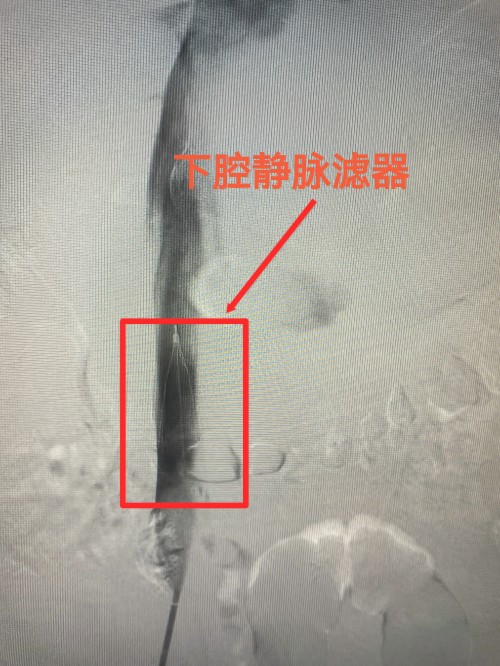

时间就是生命!30分钟后,何大爷被推入介入手术室。田壮博带领团队紧急为何大爷施行下腔静脉造影+下腔静脉滤器置入术+肺动脉造影+肺动脉碎栓、溶栓术,手术仅耗时50分钟。术中,田壮博副主任医师团队首先在患者下腔静脉置入滤器,防止血栓再次脱落造成肺栓塞,随给予肺动脉碎栓、溶栓疏通阻塞的肺动脉。手术结束后患者血氧饱和度立即上升至98%,胸闷、呼吸困难症状明显好转。